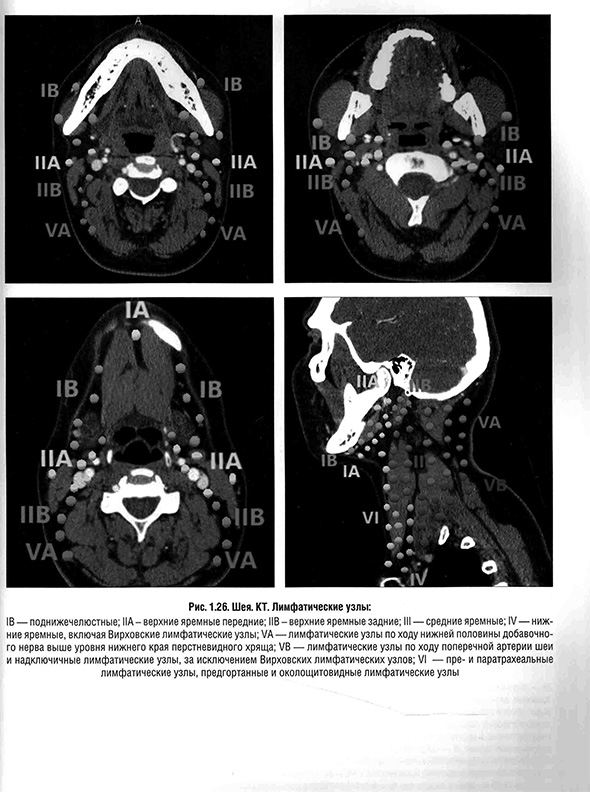

Глава 10. Лучевая диагностика заболеваний лимфатических узлов